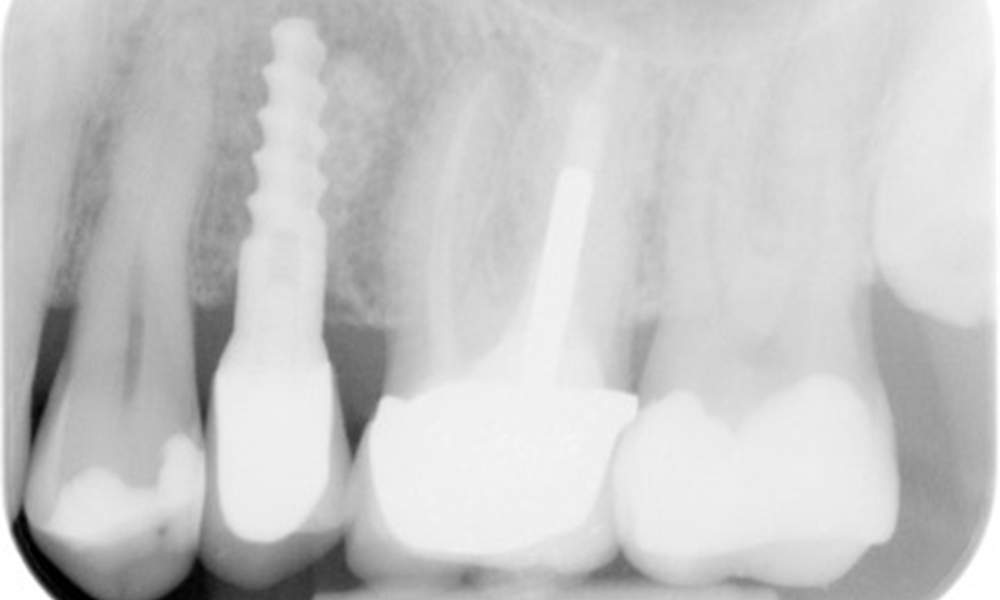

The X-ray image shows the bone loss

The X-ray images show the bone loss.

X-ray images (or bitewing X-rays) taken on: 18/02/2021